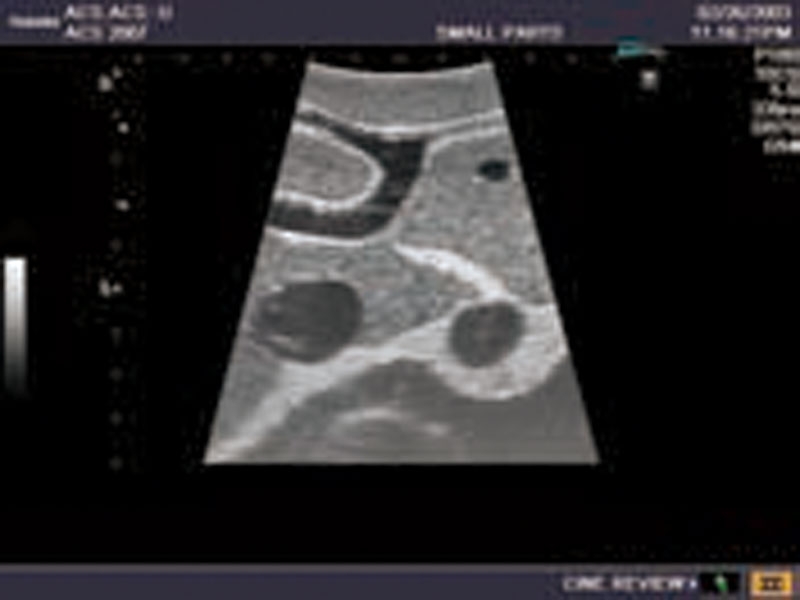

Ultraschall-Modell für die intraoperative abdominelle und laparoskopische Sonografie Eigenschaften

- Ein künstliches Modell für die Ausbildung eines Anfängers nach Demonstration durch einen Fachmann.

- Die genaue Darstellung der Anatomie der Leber und Gallenwege, des Pankreas und des übrigen Abdomens entspricht den höchsten Anforderungen an eine exzellente Ausbildung: offene intraoperative Sonografie von Leber, Gallengängen und Pankreas; die laparoskopische Untersuchung des Gallensystems zur Prüfung auf eine Steinbildung und Beurteilung auf Leber- und Pankreasläsionen etc.

- Die weichen Materialien des Modells ermöglichen eine realistische Sondenführung. Verschiedene Läsionssimulationen wie Gallensteine und -zysten, solide Tumore (echoarm, echoreich, entsprechend der Echostruktur des simulierten Objekts) in Leber, Pankreas und Nieren.

Die pathologischen Befunde umfassen:

Läsionen der Leber (solide und zystische), Gallenblasen- und Gallengangssteine, Pankreastumore (einer dringt in die Portalvene ein), Läsionen der Milz und beider Nieren, Nebennierentumor links.